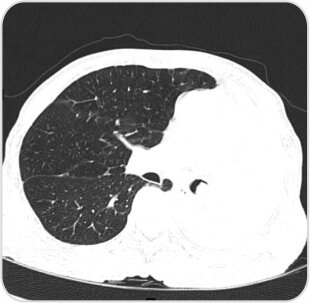

Pre procedure CT image showing collapsed left lung with occluded left main bronchus